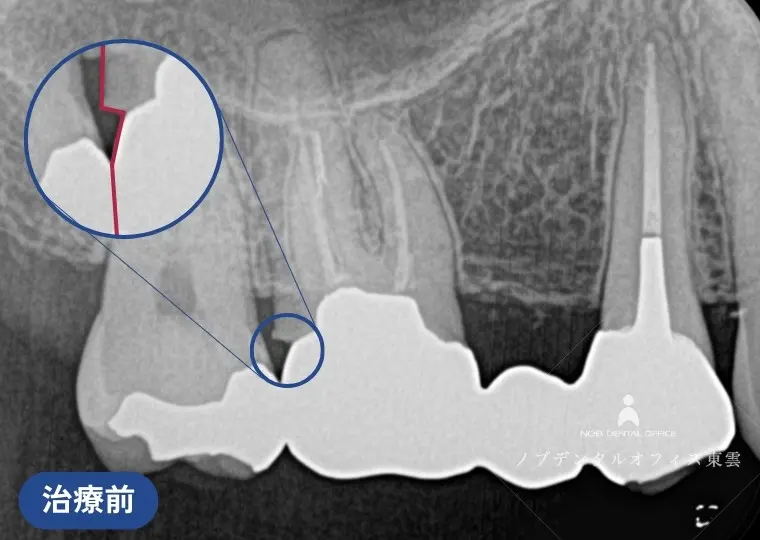

ブリッジの再治療をジルコニアで行った症例(40代女性)

右上の奥歯にすでに保険適用の金属のブリッジが入っていました。

| 治療 | ・根管治療の再治療 ・歯周外科処置(歯ぐきの形態修正) ・ジルコニアブリッジ |

| 費用 | かぶせ物の費用:143,000円×3本 保険適用 |

| リスク | ・経年的に摩耗が起こることがあります。 ・強い噛みしめや歯ぎしりにより、欠けたり外れる可能性があります。 ・歯ぐきの状態によっては境目が見えてくる場合があります。 ・清掃状態や生活習慣によっては境目から虫歯や歯周病が起こることがあります。 |